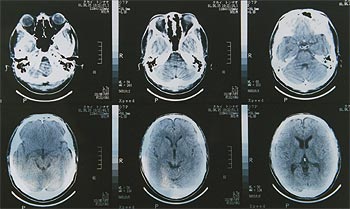

特に5について後の生理研での講義内容を予想し,比較的ていねいに取り扱った.また,生体膜の物質輸送に関する研究室訪問に備え,静止電位・活動電位発生のメカニズム(ナトリウムポンプ,ナトリウムチャネルなど)の説明も加えた.さらに,磁気による脳の実験施設見学の興味づけに私の頭部CT像(写真1)を使い脳や眼球の断層面のようすを観察し,ブタの脳の解剖実習に入った.

写真1 CT像